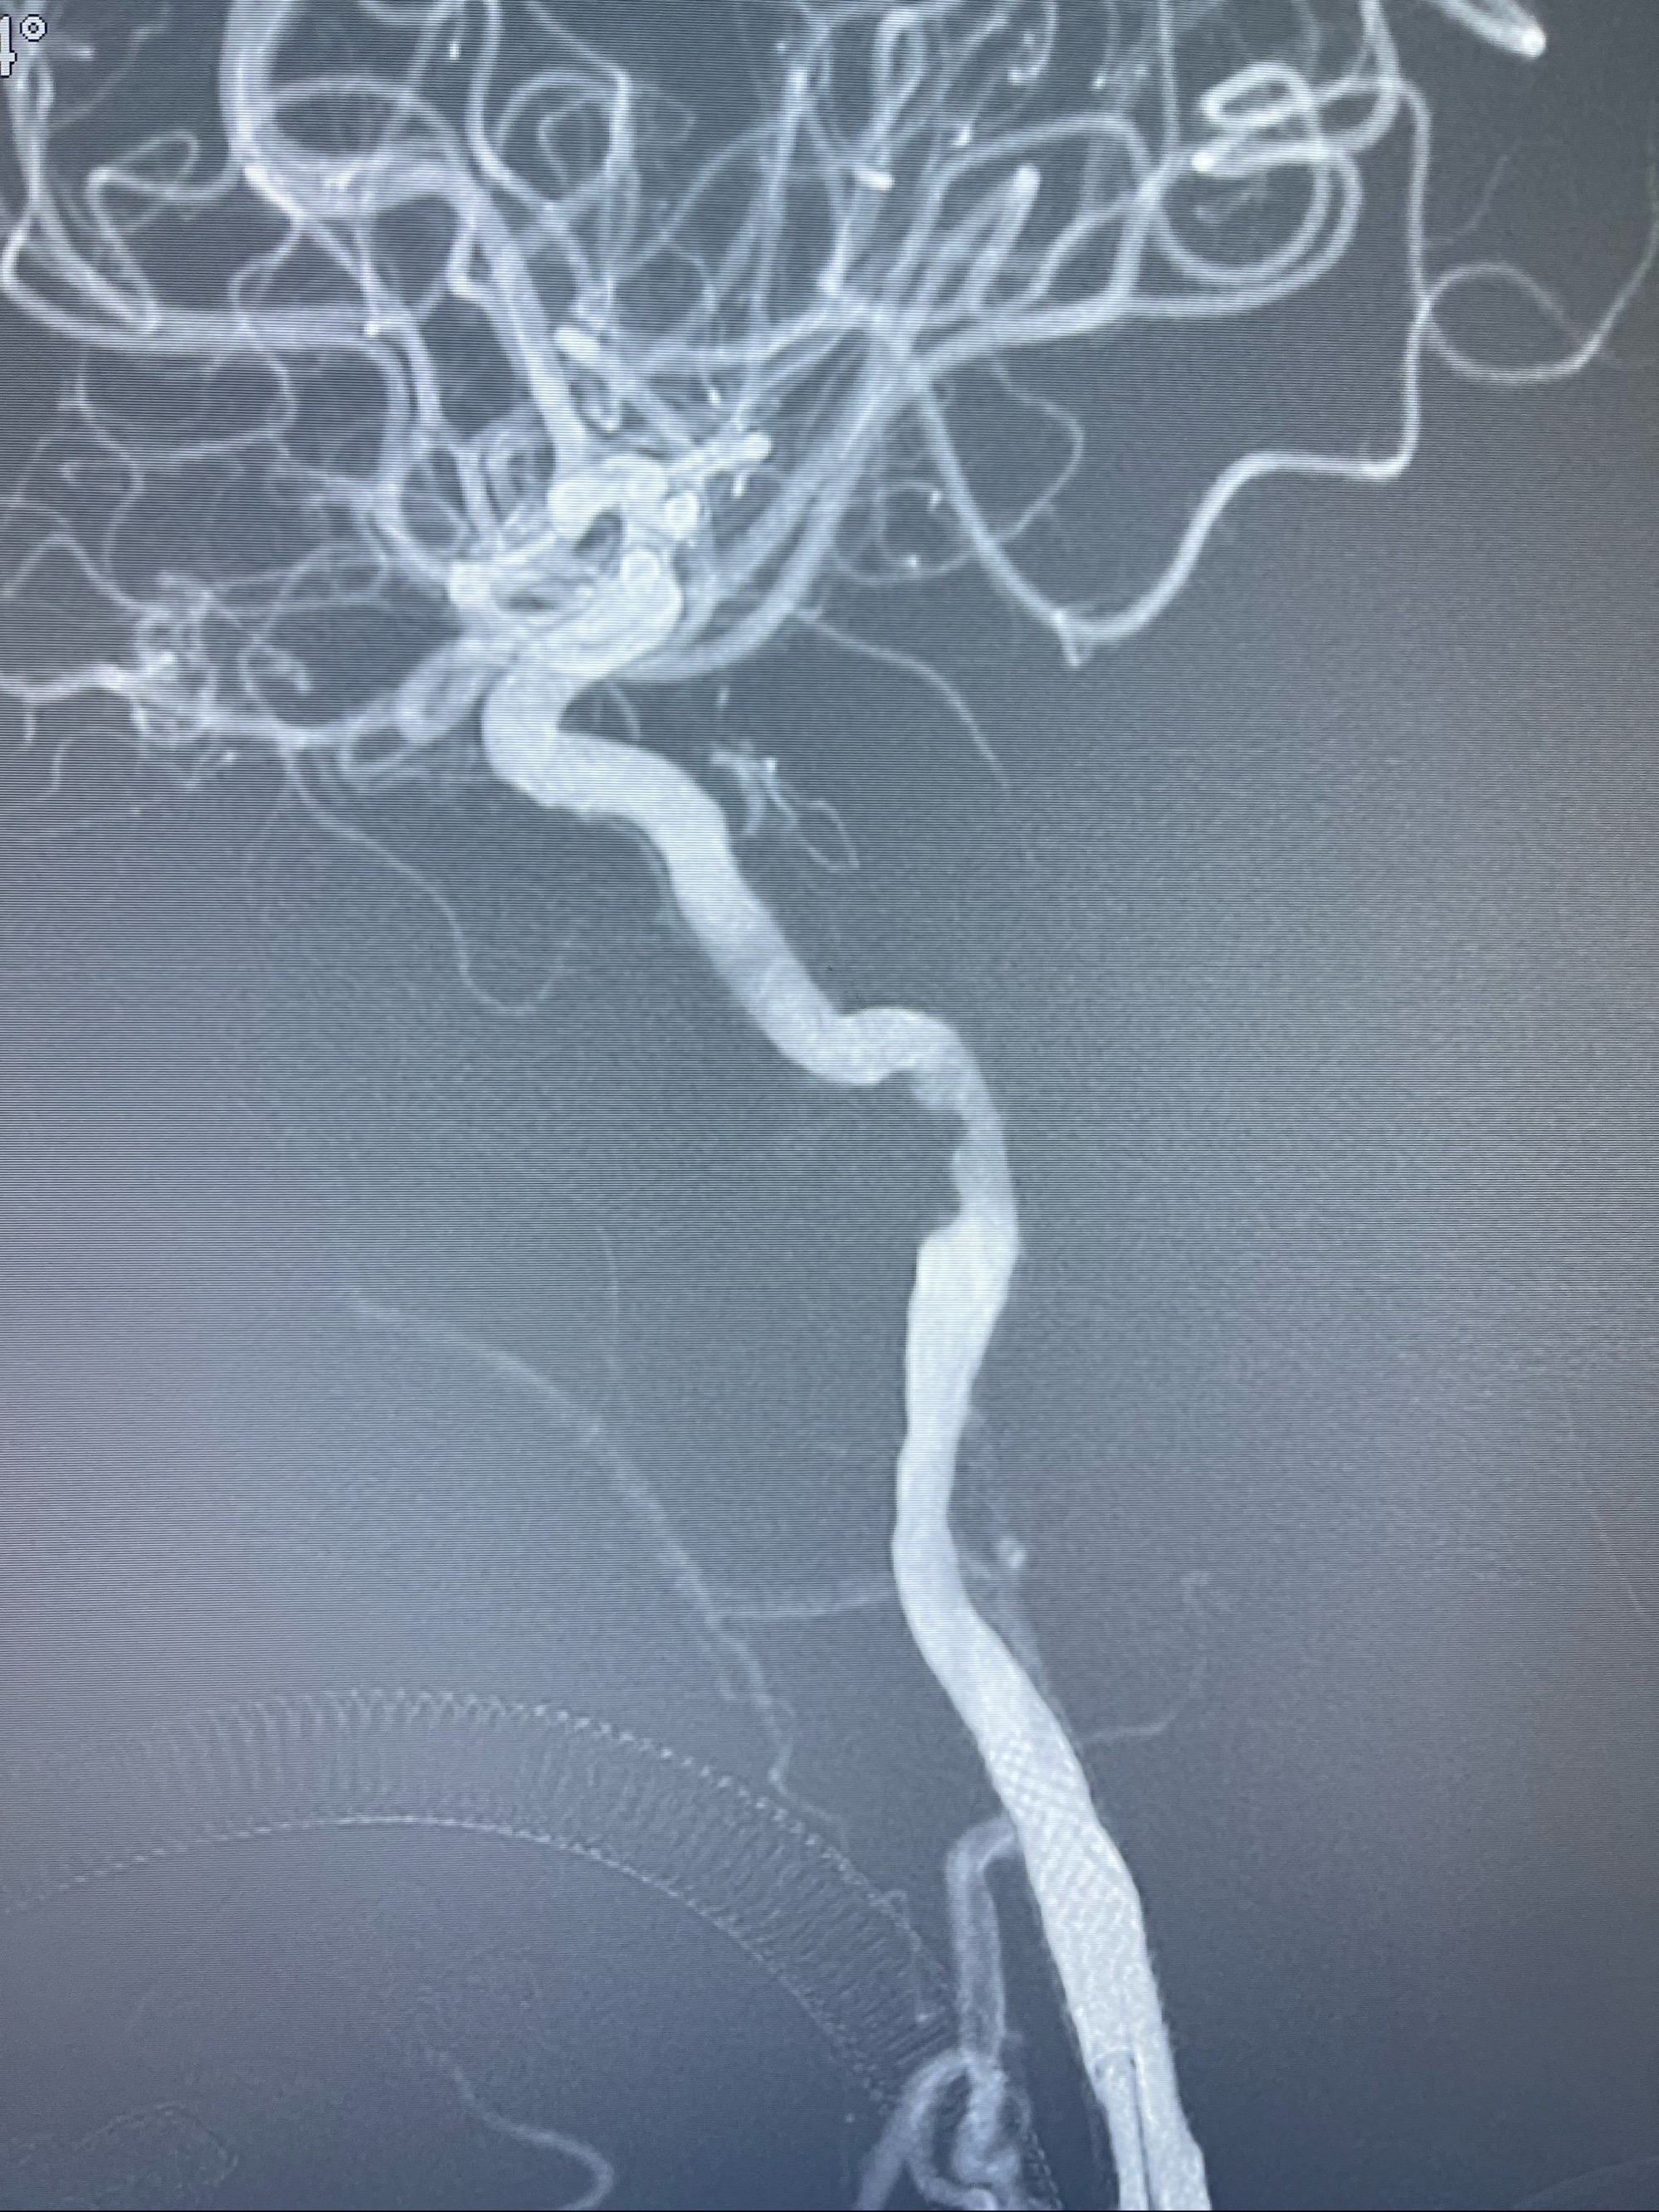

2023-07-10DSA:右侧颈内动脉岩骨段夹层伴中偏重度狭窄改变,左侧颈总动脉闭塞、右侧颈外动脉由右侧肋颈干甲颈干吻合代偿

箭头所示为颈内动脉岩骨段重度狭窄,结合MRI,考虑为肿瘤侵犯右侧颈内动脉

箭头以近至支架段管腔不规则狭窄